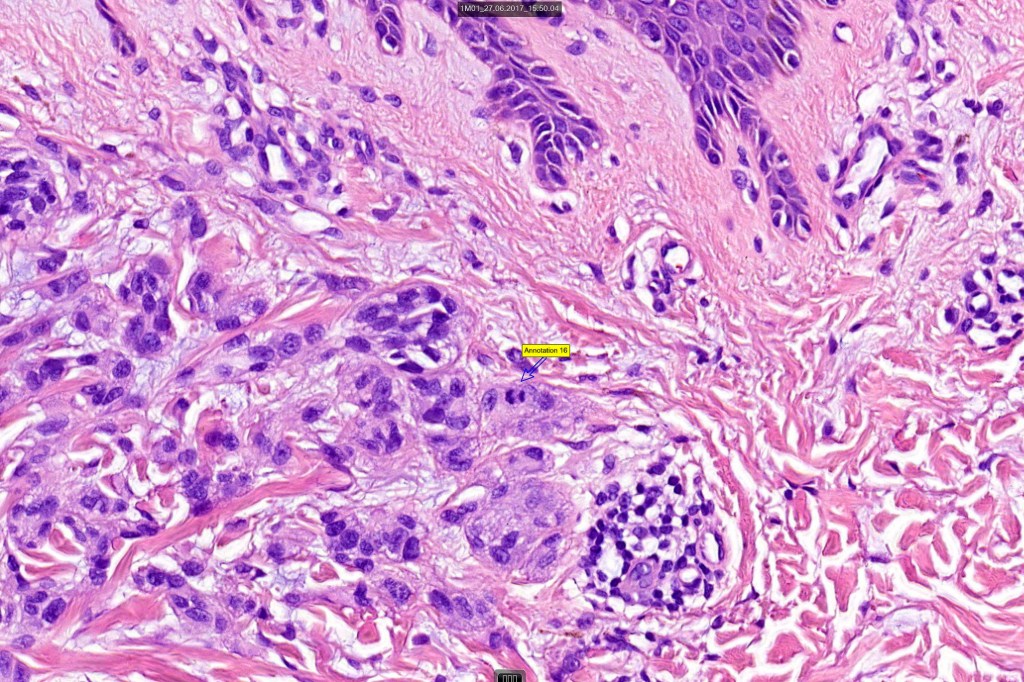

Histological features

•Verrucous or dome-shaped, at low power, the lesion looks like a nevus

•Minimal or no junctional component

•Expansile nodules or diffuse

•Compression of connective tissue

•Subtle or not so subtle impaired maturation with depth (sometimes this is evident at scanning magnification)

•Subtle nucleolar prominence

•Subtle pleomorphism

•Mitoses invariable including often in the deep aspect